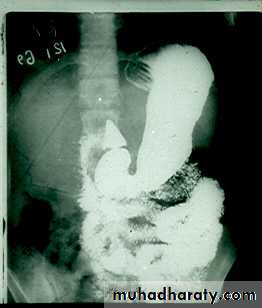

Hypertrophic pyloric stenosisCause:A. Congenital typeB. Adult type

GIT